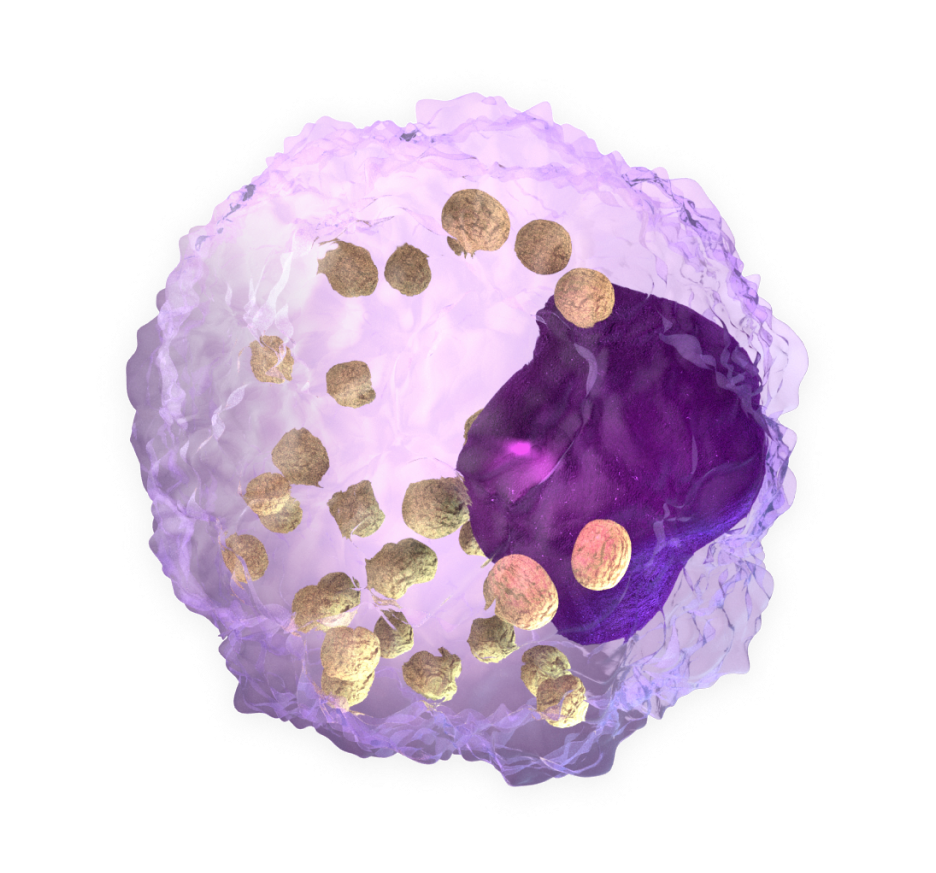

CAR-Macrophage cells

are specially engineered to fight cancer

Chimeric antigen receptors (CARs) are designed to redirect the effector function of immune cells against tumor targets.

Expression of these receptors in macrophages refines tumor recognition and improves phagocytic capacity.

The CAR-M therapeutic approach uses the ability of macrophages to infiltrate solid tumors and travel through the hostile tumor microenvironment to access tumor cells, eliminate them and activate an adaptive response.